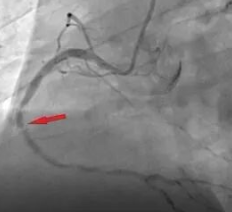

c.造影显示血管病变。如果造影显示血管狭窄到一定程度,医生会建议您做球囊扩张或支架植入术。